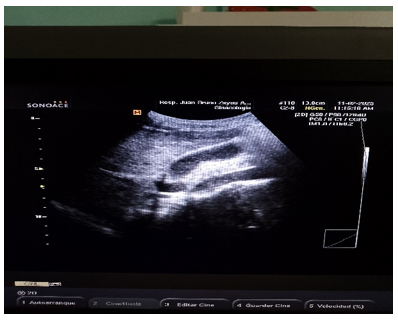

Ultrasonido Abdominal:

Hígado de tamaño normal, eco estructura homogénea, vías biliares no dilatadas, vesícula de tamaño normal con múltiples elementos alargados en su interior que impresiona parasitismo, conducto cístico tortuoso y dilatado hasta su unión con en el hepático común páncreas normal. Riñón izquierdo y derecho, ambos de tamaño y posición normal. Aorta y área de las suprarrenales normales, quiste en el ovario izquierdo sin repercusión.

Ultrasonido de Hemiabdomen superior (Confirmatorio).

Similar a la anterior, vesícula 78 x 19 x 20 mm con paredes normales y elementos ecogénicos alargados en suspensión que recuerda un parasitismo intestinal (Ver Figura 1, 2).

Figura 1

Figura 2

(Fuente propia de los autores)

La terapia antihelmíntica generalmente no se administra durante la fase pulmonar porque la eficacia de los fármacos contra las larvas en los pulmones es incierta. El uso de albendazol fue indicado como terapia complementaria por su excreción principalmente biliar; tanto en este caso como en otros pacientes como aparece informado en artículos médicos (5, 7). En el caso de Vargas-gallego. et al. (1) mostraron la importancia del estudio ecográfico para el diagnóstico de ascaridiasis errática hepato–biliar, presentándose formas ecográficas como el signo de ojo de buey que implica enrollamiento del parásito, el signo de la raya que es por una delgada raya sin tubo interno, y como en nuestro caso el signo del espagueti, cuando hay superposición longitudinal de parásitos en la vía biliar debido al enrollamiento de uno o varios áscaris.